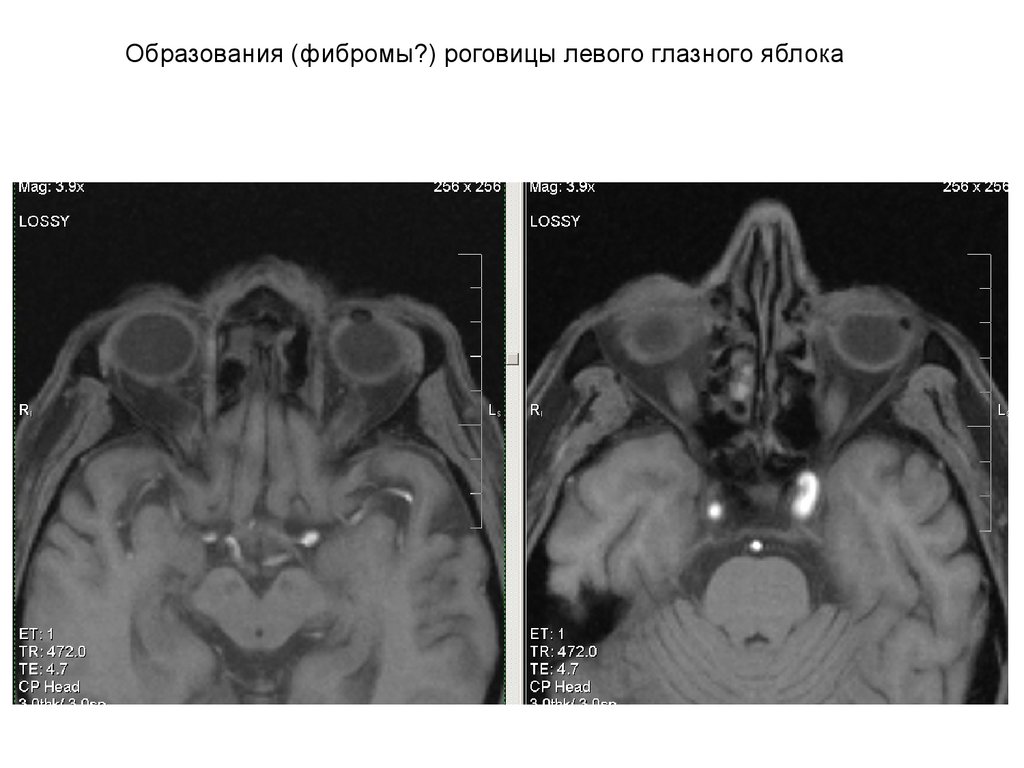

Образования (фибромы?) роговицы левого глазного яблока